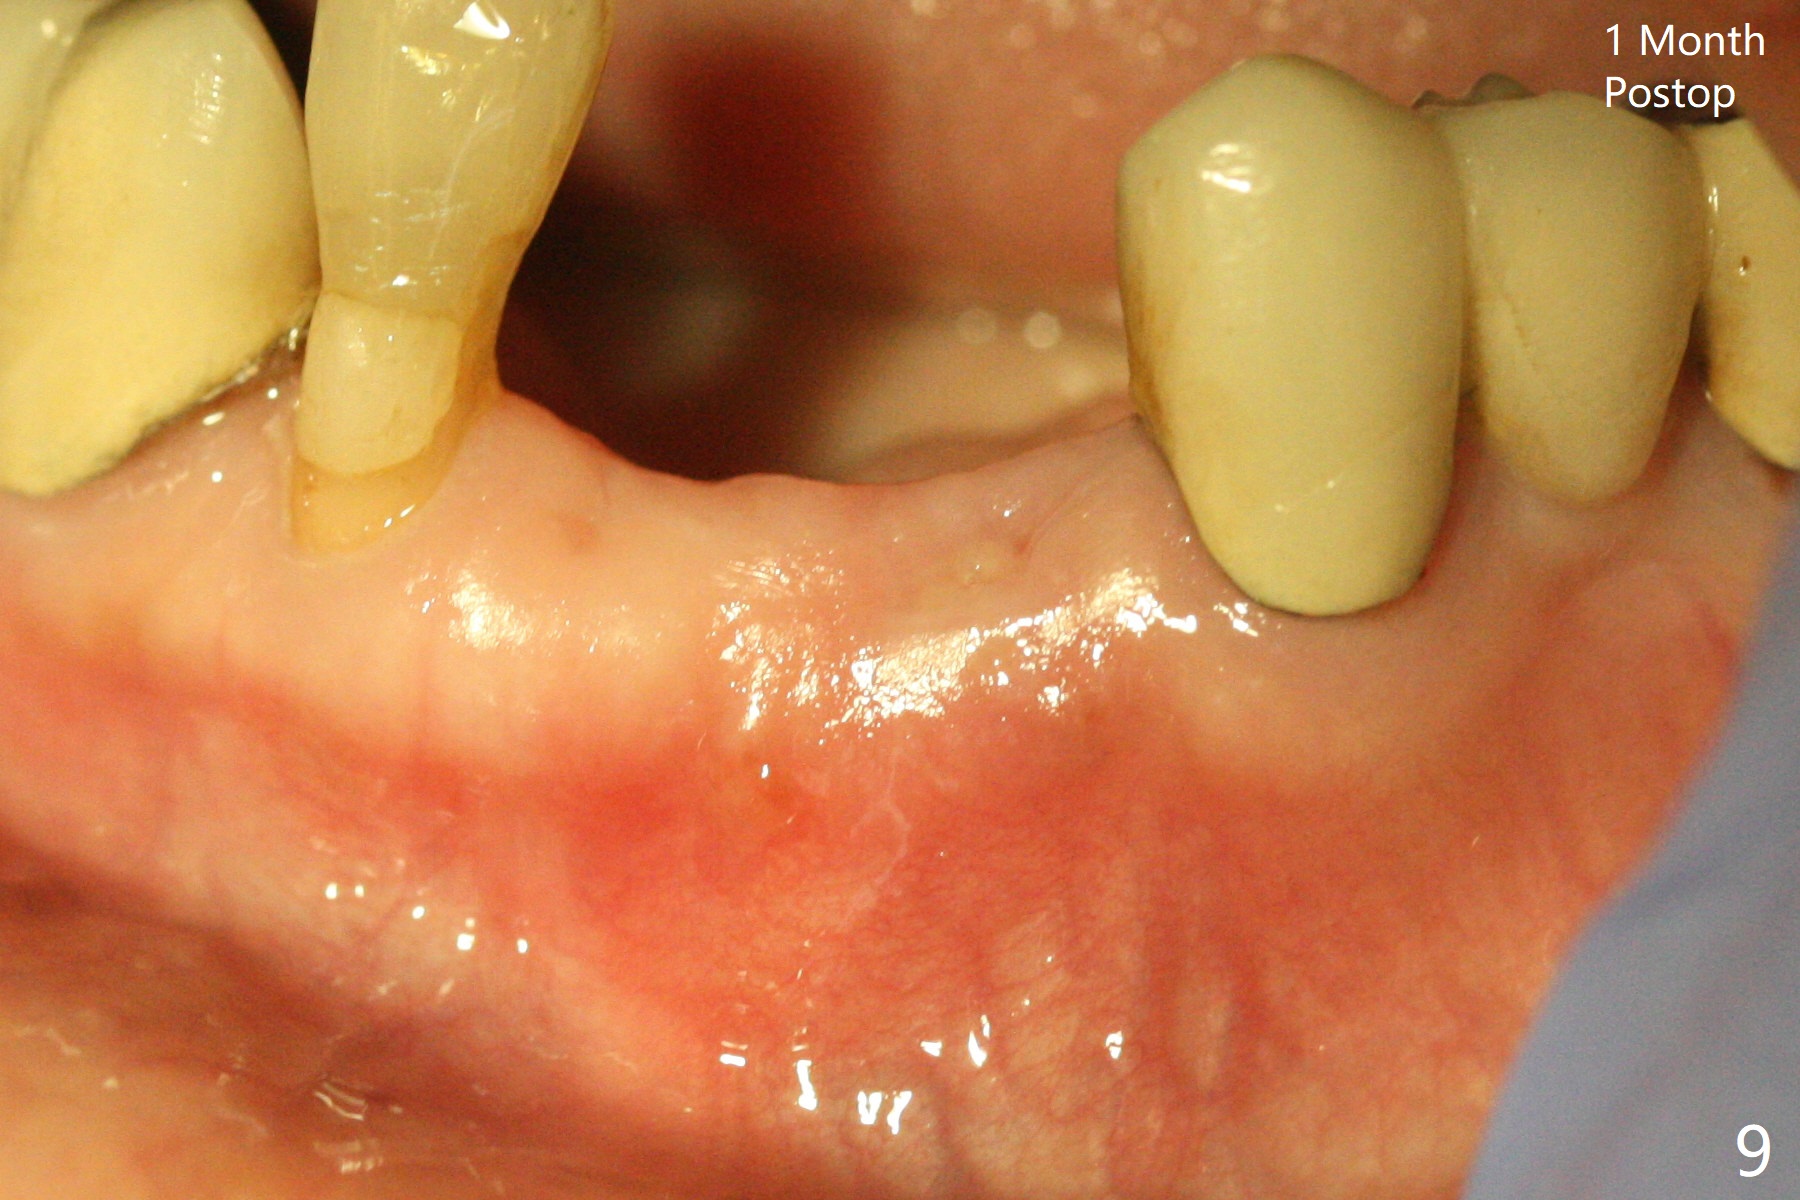

A 64-year-old woman requests extraction of the tooth #23 for lower partial (Fig.1). Since there are 2 buccal sinus tracks, another residual root is suspected (?). After shown loss of the buccal plate (Fig.2,3), the patient agrees to have socket preservation with allograft (Fig.5,6 *) and BioXclude (Fig.4 >). The suspected residual root is not explored considering the 2 sinus tracks being associated with the lesion of #23 (Fig.2,3). Cytoplast is not used because of time constraint and fear of gingival dehiscence associated with extensive dissection. In fact the sinus tracks shrink in a week, while the buccal plate remains bulging (Fig.7 *) and the socket heals (Fig.8 >). The buccal plate is flat (no swelling) 1 month postop (Fig.9).